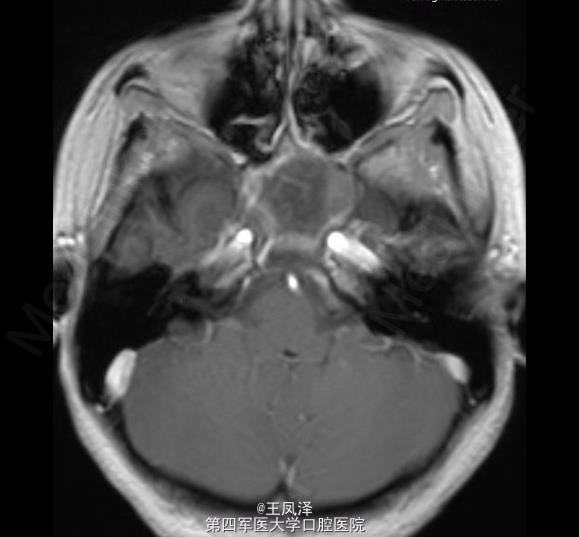

蝶窦粘液囊肿一例

女性,20 岁,在 18 个月大时诊断为自闭症和智力迟钝,目前发生多次抽搐现象,可能为癫痫发作。